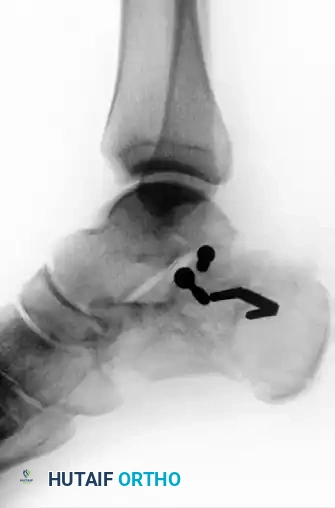

Figure 88-11D: Postoperative axial radiograph confirming restoration of heel width and correction of varus malalignment.